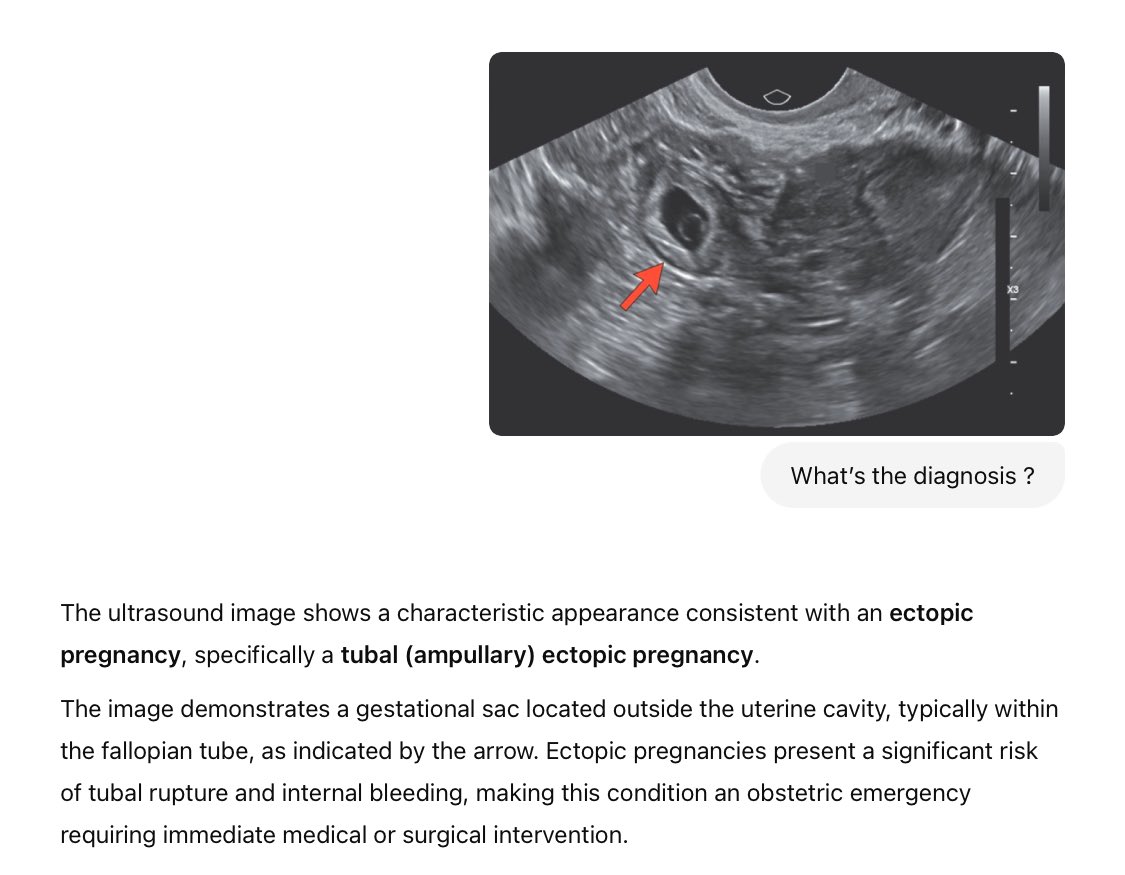

Others, such as biomedical scientist and Professor Derya Unutmaz of The Jackson Laboratory, claimed that GPT-4.5 “appears to be remarkable” in medical image diagnosis — correctly spotting a tubal ectopic pregnancy.

Other AI models, such as Grok 3, Claude 3.7 Sonnet, Gemini 2.0 and earlier ChatGPT models, mistakenly identified a medical image as a normal pregnancy, Prof. Unutmaz said.